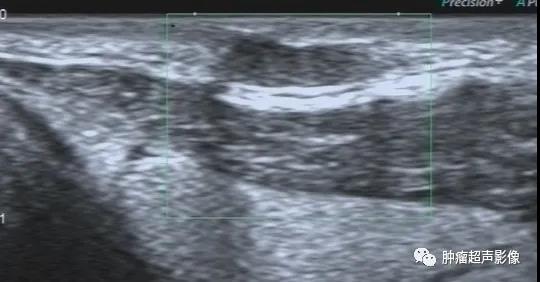

病理证实的脂囊瘤:颈部皮下单发低回声,边界清、形态规则,后方回声增强,CDFI无血流,符合囊肿表现,与表皮样囊肿超声表现相似。